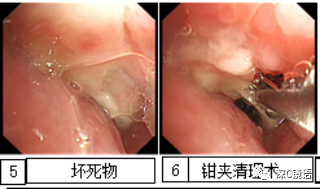

医疗方面:目前,我科室能开展呼吸内镜相关诊断与治疗技术,具体如下:诊断技术包括经支气管镜冲洗术、灌洗术、刷检术、活检术、针吸活检术、环形超声以及内科胸腔镜等;治疗技术包括球囊扩张术、支架植入术、高频电凝术、高频电圈套治疗、激光治疗、冷冻治疗、局部注药治疗等。秉承“患者所需,医者所为”的宗旨,为肺部感染、肿瘤、气道异物、不明原因胸腔积液,尤其是气道结核的患者,提供综合诊治方案。